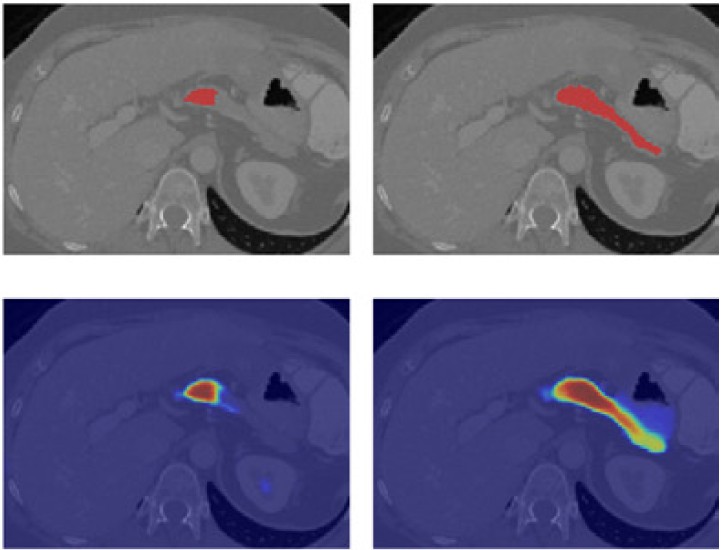

Sycai Medical develops an AI-powered assistant that detects pre-cancerous lesions at a benign stage. It helps radiologists monitor lesions by characterizing them and comparing new images with previous scans to track evolution.